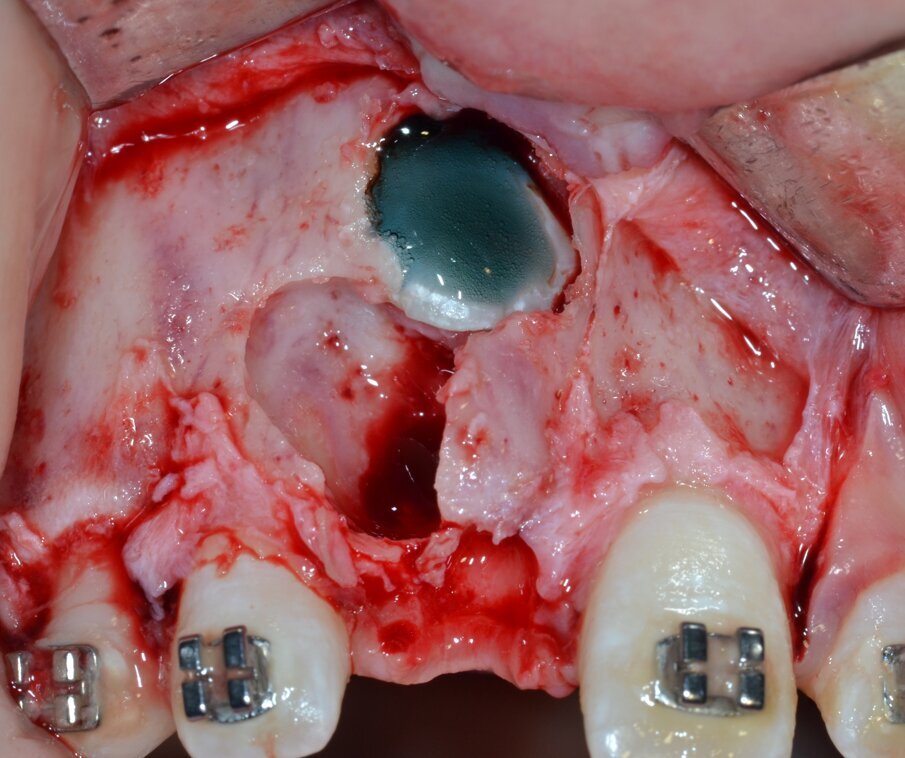

La neoformazione viene aggredita in due tempi operatori distinti: il primo tempo consiste nell’ostectomia per erosione della corticale ossea che la ricopre integralmente (Fig. 6) e, successivamente, viene effettuata un’osteotomia perilesionale alla ricerca del piano di clivaggio tra la neoformazione e il tessuto osseo circostante (Fig. 7).

Poiché l’odontoma composto non ha un perimetro regolare, durante questo tempo operatorio va posta la massima attenzione nel seguirne accuratamente i contorni: questa precauzione diminuirà il rischio di effettuare un’osteotomia eccessivamente demolitiva.

Allo scopo di favorire il controllo tattile e migliorare la visibilità intraoperatoria da parte dell’operatore, le fasi sopra descritte vengono eseguite mediante inserti piezoelettrici dedicati montati su manipolo ad ultrasuoni (ES009T e ES010T Esacrom Srl, Imola, Italia)3.

Fig. 6_Ostectomia per erosione della corticale ossea.

Fig. 7_Osteotomia perilesionale che segue il contorno della neoformazione.